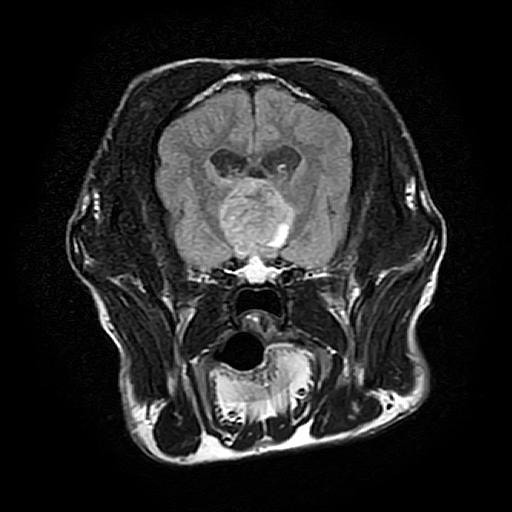

MRI画像:クッシング症候群の犬の下垂体腺腫

上記のような症状が認められた場合、まず血液検査・腹部X線検査などにより、除外診断を行います。臨床症状を含め、特徴的な所見が認められた場合、クッシング症候群の確定診断のためACTH負荷試験と呼ばれる検査を行います。状況により、エコー検査、CT/MRI検査を行い、コルチゾール分泌に関わる下垂体や副腎の状態を確認します。クッシング症候群と診断された場合は、お薬によるコントロール、原因によっては外科手術などが必要となってきます。